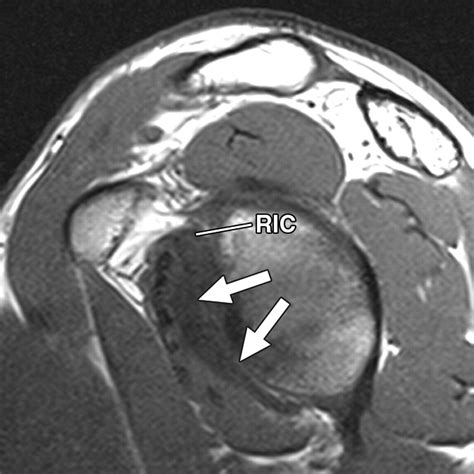

The rotator cuff interval is a triangular space located in the anterior-superior aspect of the shoulder joint. It is bordered by the superior margin of the subscapularis tendon and the anterior margin of the supraspinatus tendon. The base of this triangle is formed by the coracoid process, while the apex extends toward the intertubercular groove of the humerus. Several vital structures traverse this interval, playing a pivotal role in shoulder stability:

• Coracohumeral Ligament (CHL): A primary stabilizer that prevents inferior translation of the humeral head.

• Superior Glenohumeral Ligament (SGHL): Provides resistance to external rotation and helps secure the humeral head.

Accurately diagnosing conditions affecting the rotator cuff interval requires a combination of physical examination and advanced imaging. Physicians typically begin with clinical tests to isolate the function of the biceps tendon and the rotator cuff muscles. However, because the interval is deep, imaging is vital for a definitive diagnosis.

Magnetic Resonance Imaging (MRI) The gold standard for visualizing soft tissue, ligamentous thickening, and interval tears.